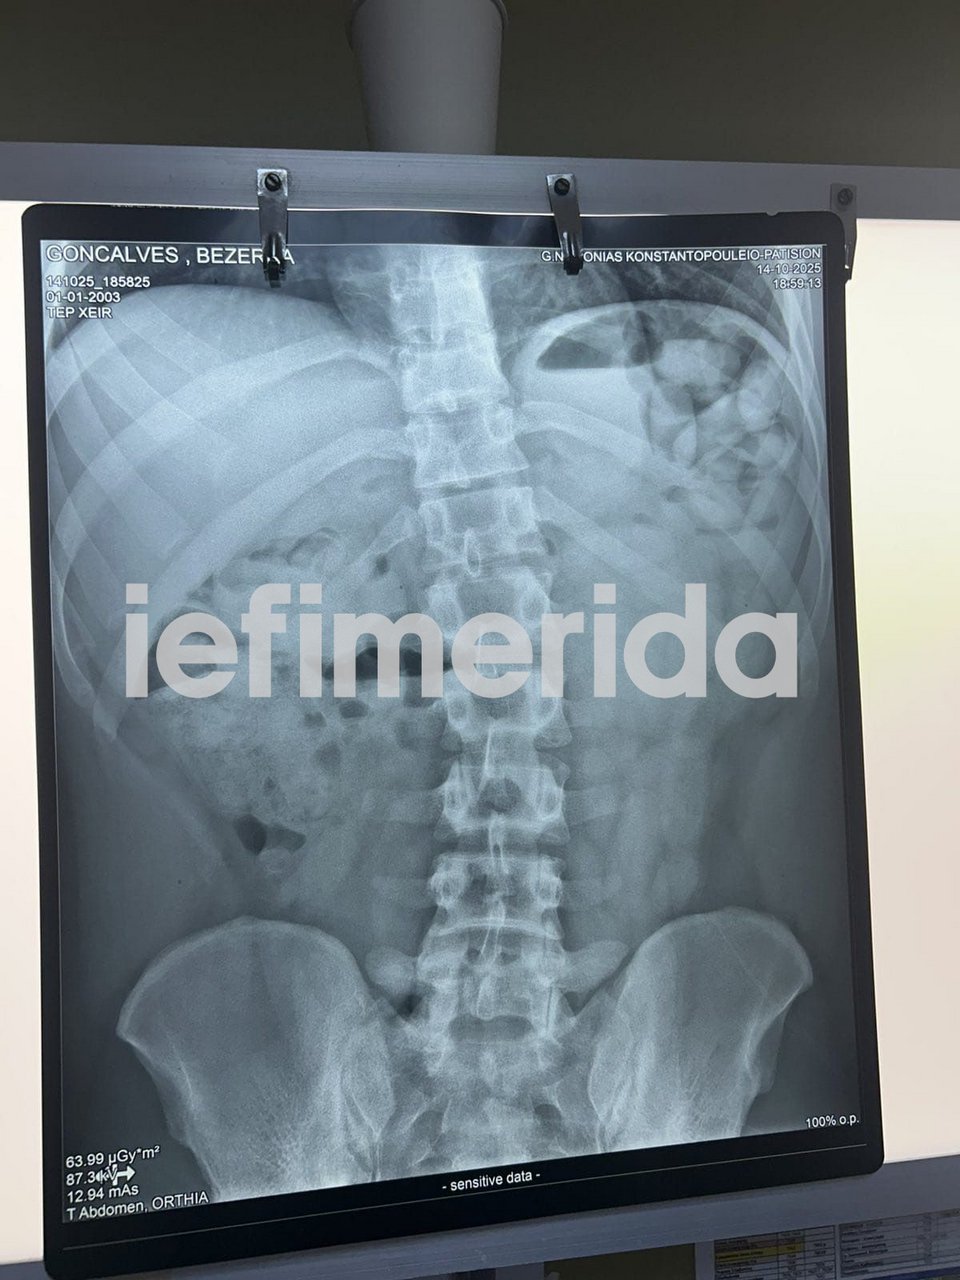

Ο 22χρονος έφτασε αεροπορικώς από το Παρίσι και, όπως διαπιστώθηκε από τον έλεγχο, είχε καταπιεί όχι μία, όχι δύο αλλά 72 αυτοσχέδιες ωοειδείς συσκευασίες με τα 840 γραμμάρια της κοκαΐνης.

Οι αστυνομικοί περίμεναν μέχρι να τις αποβάλει διά της φυσικής οδού και προχώρησαν στην κατάσχεσή τους.